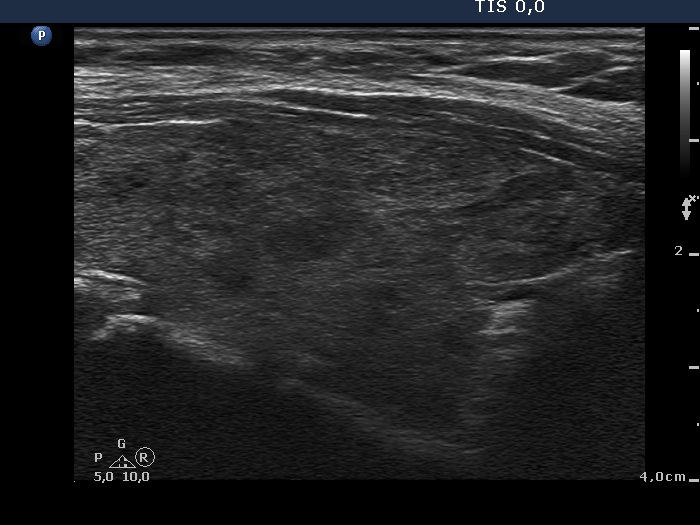

An operated thyroid - Case 1. A patient with an unilateral subtotal thyroidectomy

Three years after surgery (ultrasonographic picture 3)

Lower part of the right lobe, longitudinal scan.